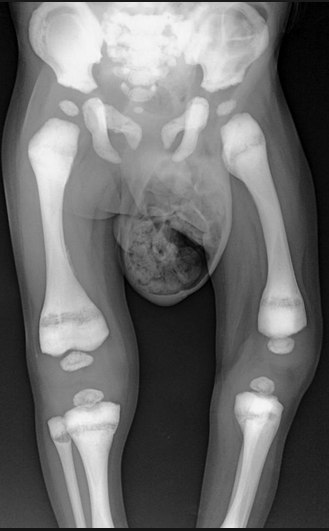

3 radiographic findings in osteopetrosis

Rugger jersey spine

Erlenmeyer flask distal femur

Thickened cortex/lack of a IM canal